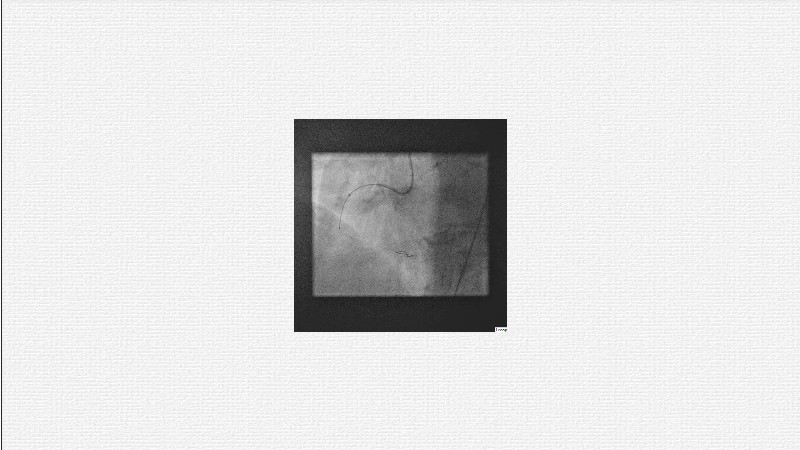

This EuroPCR 2025 session challenges the conventional approach to bifurcation PCI and dissection management. Learn why drug-coated balloons (DCB) may offer better long-term outcomes in cases where stents fall short, how DCBs can simplify bifurcation strategies, and why it’s time to rethink which dissections really need stenting. Through data, case examples, and clear decision-making insights, you'll gain the confidence to broaden your DCB practice where it truly matters.

- To analyse clinical data and use case of drug-coated balloons in bifurcation PCI